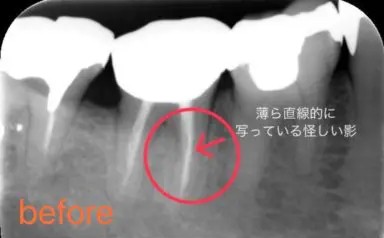

初診時の口腔内写真です。他院での根管治療の際にリーマーが折れ、歯の中に残ってしまっている症例です。

レントゲン写真をご覧ください。この直線的に写っている怪しい影が破折リーマーです。